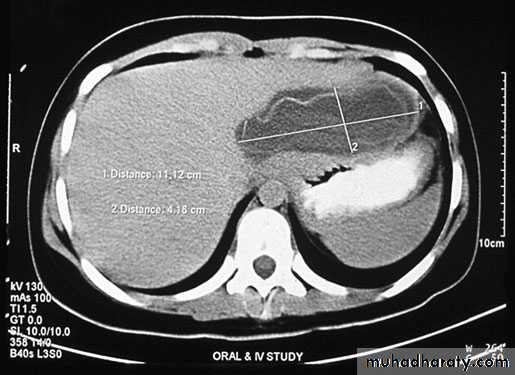

Ultrasound and CT scan are the investigations of choice. The CT scan shows a smooth space-occupying lesion with several septa .An ultrasound of the biliary tract may show abnormality in thegall bladder and bile ducts. Hydatid infestation of the biliary system should then be suspected.